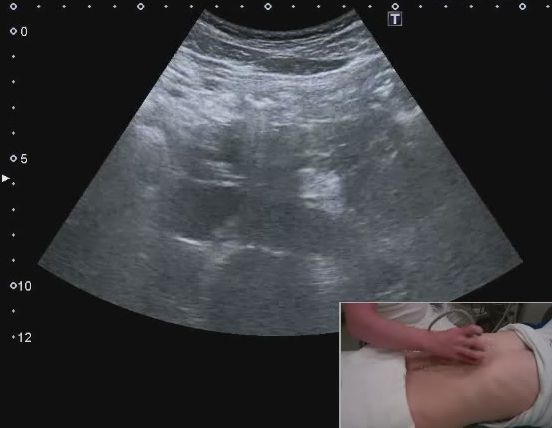

白色文字(排除指定关键词) Imaging Anatomy: interactive PACS-like atlas of radiological anatomy

解剖学模块